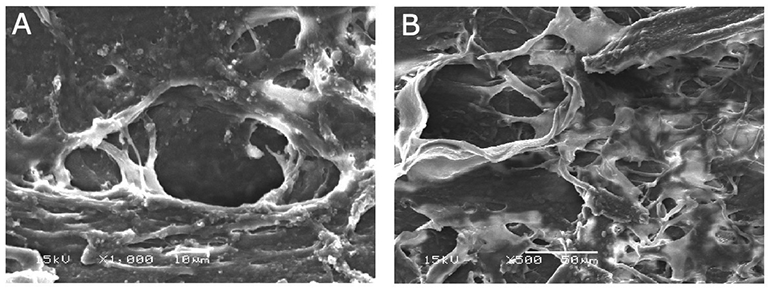

3. 섬유주소대(TM) 주변의 바탕질(Extracellular matrix, ECM)에서의 변화로,

소실된 섬유주 세포는 제거되고, 새로운 새포로 대체되게되는데,

이때 새롭게 생성된 세포는 기존의 세포와는 달리, 방수유출의 저항이 더 적은 새로운 ECM으로 대체된다고 알려져 있습니다.

이러한 ECM의 변화도 ALT의 기전 중의 하나로 알려져 있습니다.